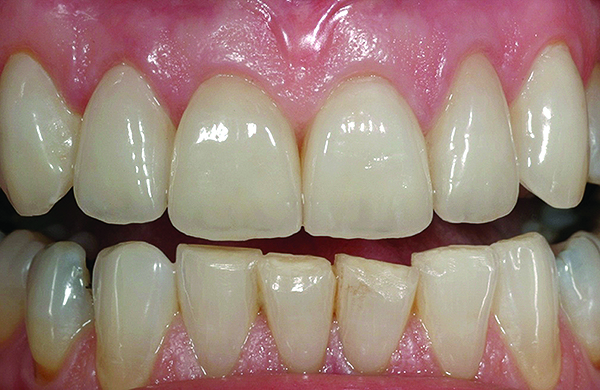

Fig 1. Preoperative (Fig 1), preparation (Fig 2), and final postoperative (Fig 3) images of a two-unit CL-I feldspathic veneer case.

Figure 1

Fig 2. Preoperative (Fig 1), preparation (Fig 2), and final postoperative (Fig 3) images of a two-unit CL-I feldspathic veneer case.

Figure 2

Fig 3. Preoperative (Fig 1), preparation (Fig 2), and final postoperative (Fig 3) images of a two-unit CL-I feldspathic veneer case.

Figure 3